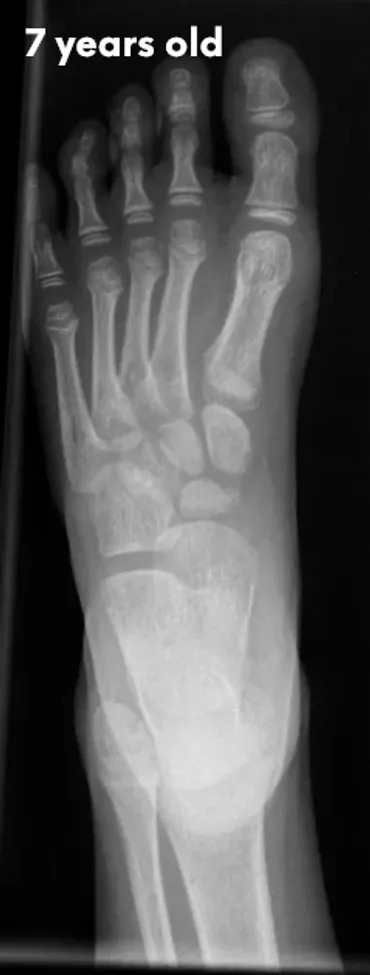

The pictures below will let you understand how babies' feet are developed. Here you can see how bones develop:

7 Years

18 YearsDear parents, children’s feet are developing structures, and the absence of an arch is a typical stage of development. Detailed X-RAY pictures above let us understand that babies' foot bones are not connected till the teen years. Only at the age of 14 may we consider that the bones in the feet have reached their connections. At the age of 18, we have fully completed foot structure, where muscles and bones create the whole support system.